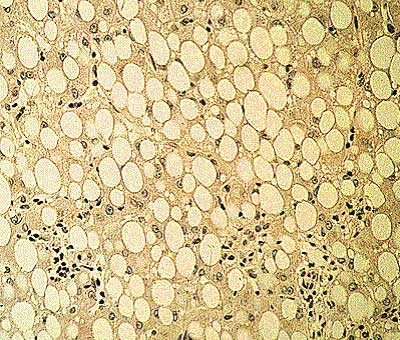

Schauen Sie sich folgende Histologie an:

Leberhistologie; Quelle: © Urban & Fischer 2003 – Roche Lexikon Medizin, 5. Aufl

Frage 4

Was sehen Sie?